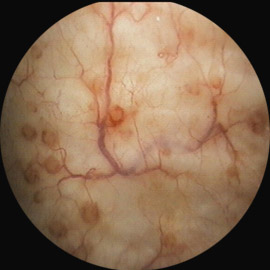

1. Кистозный цистит. Цистоскопия позволяет точно диагностировать проблему благодаря видимым изменениям. После установки диагноза лечение проводится инстиляциями лекарственными составами.